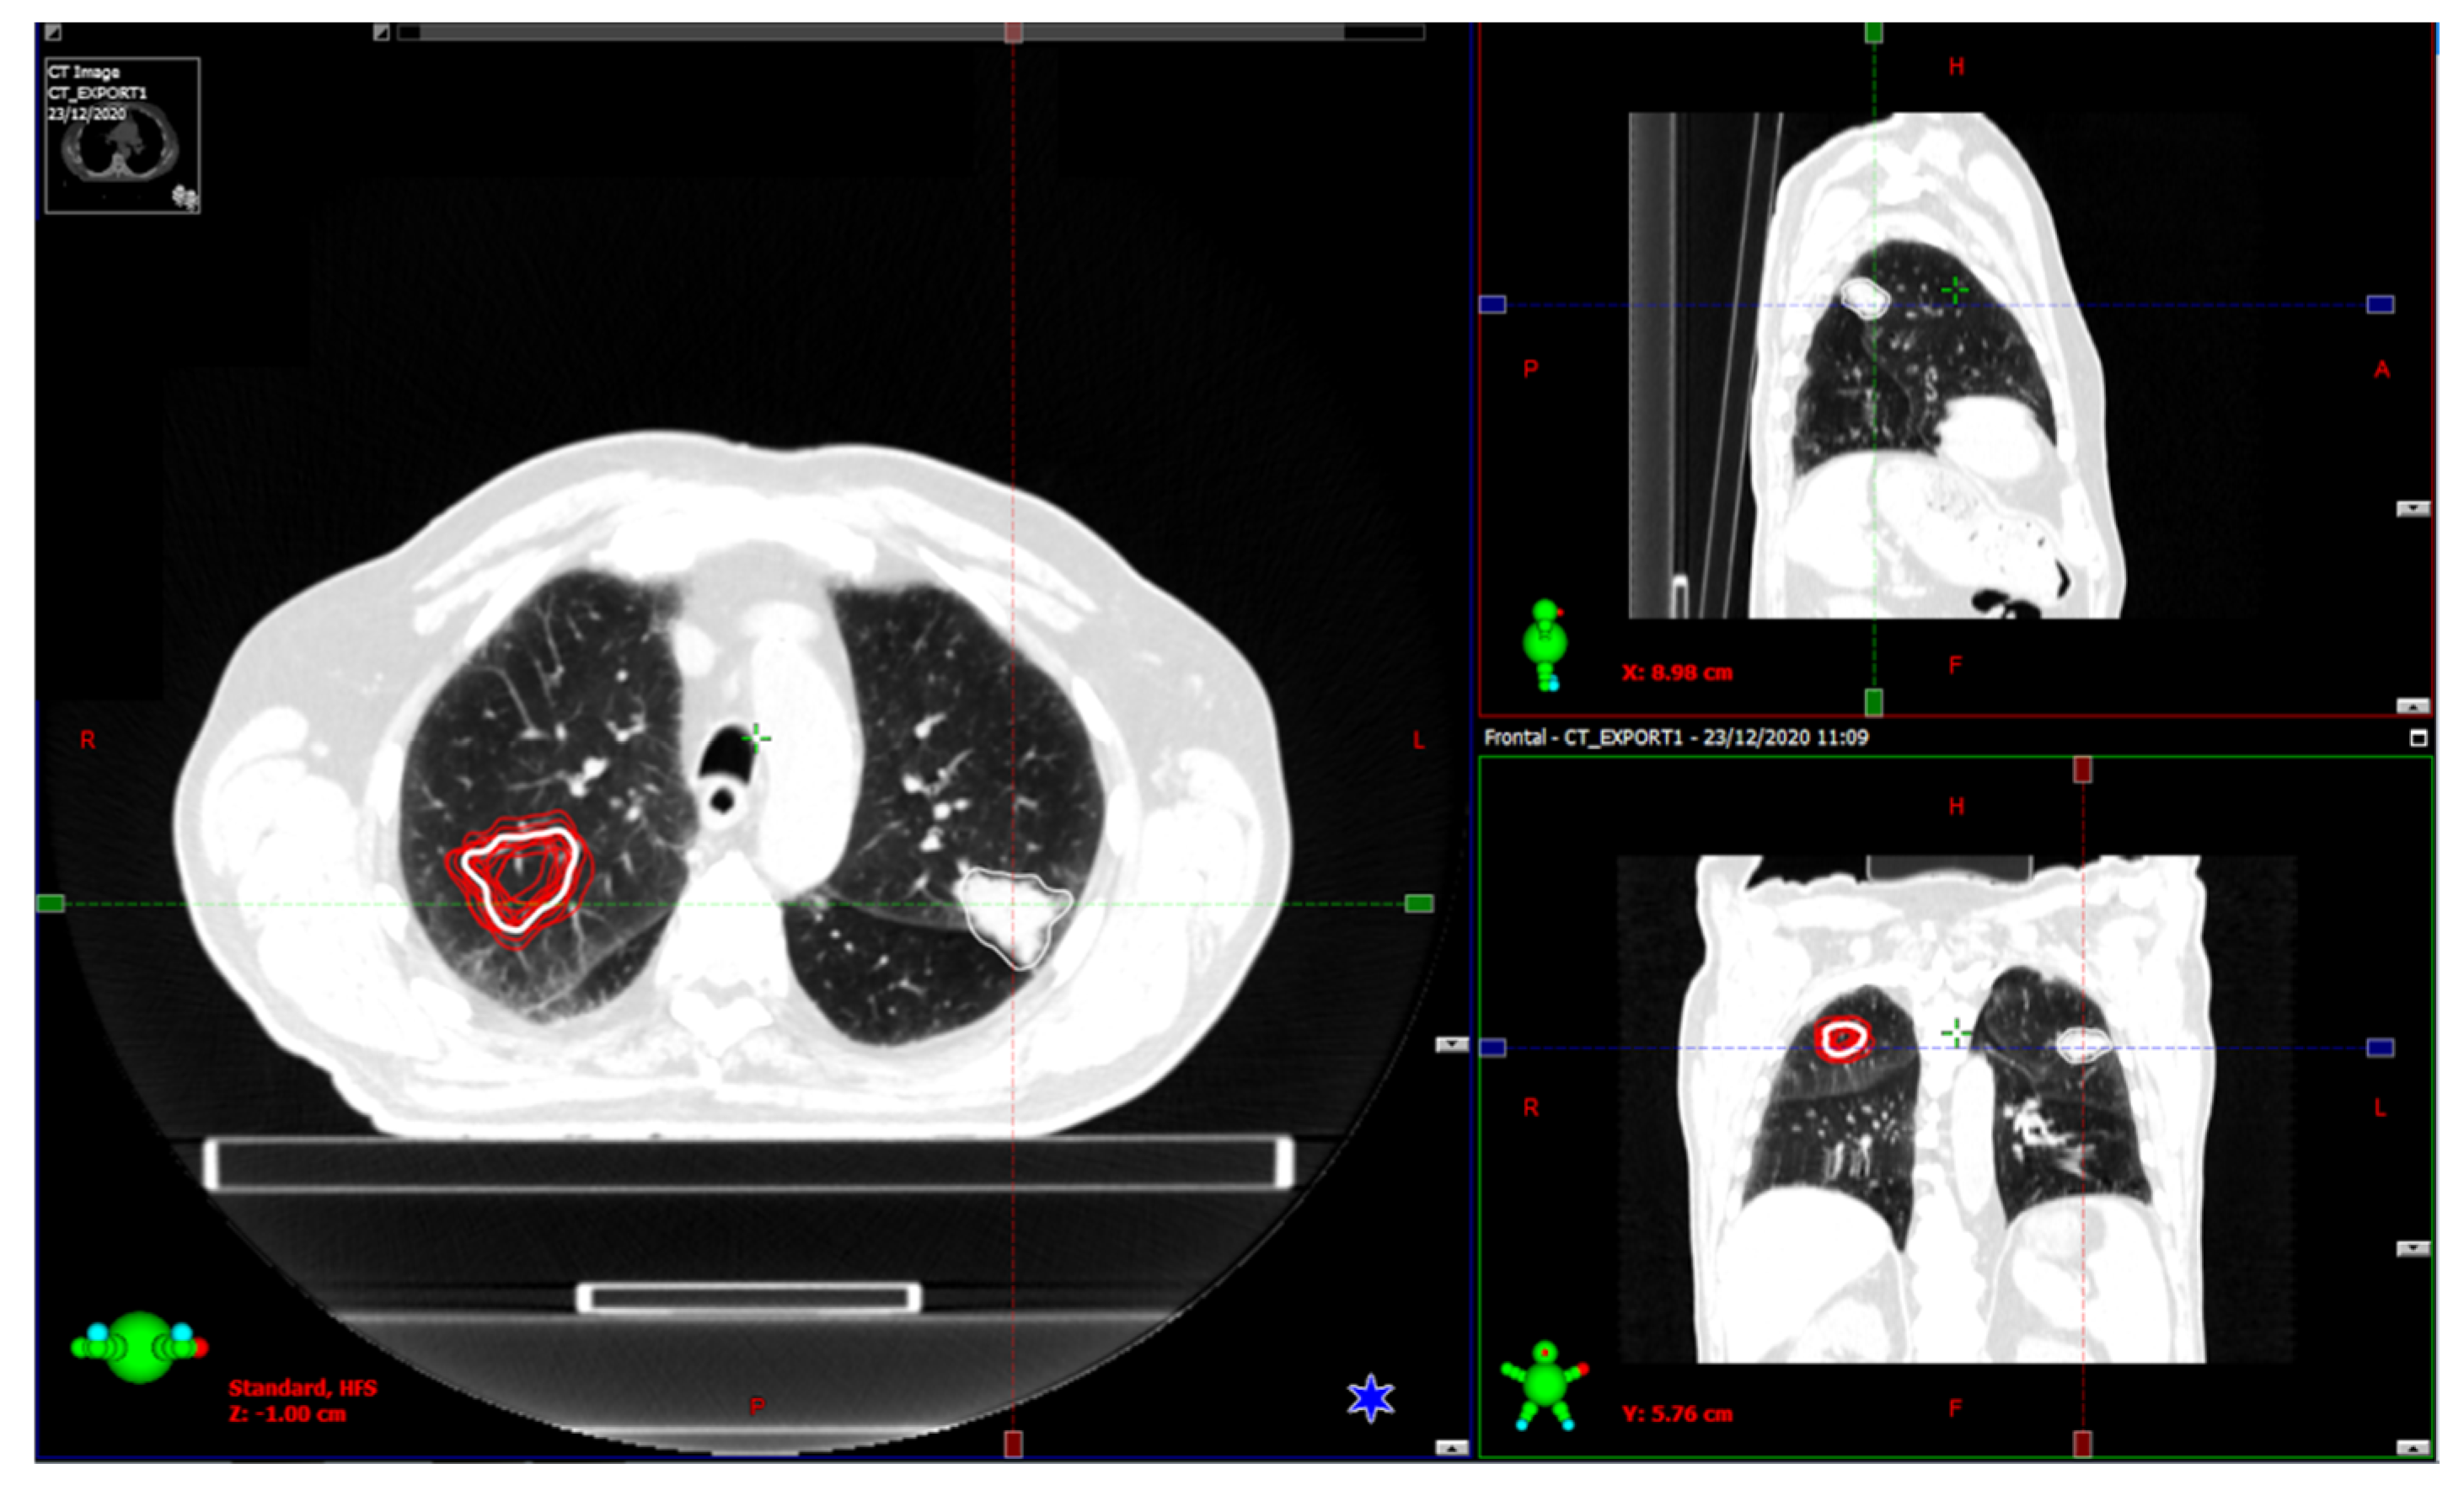

2.3. Image Segmentation